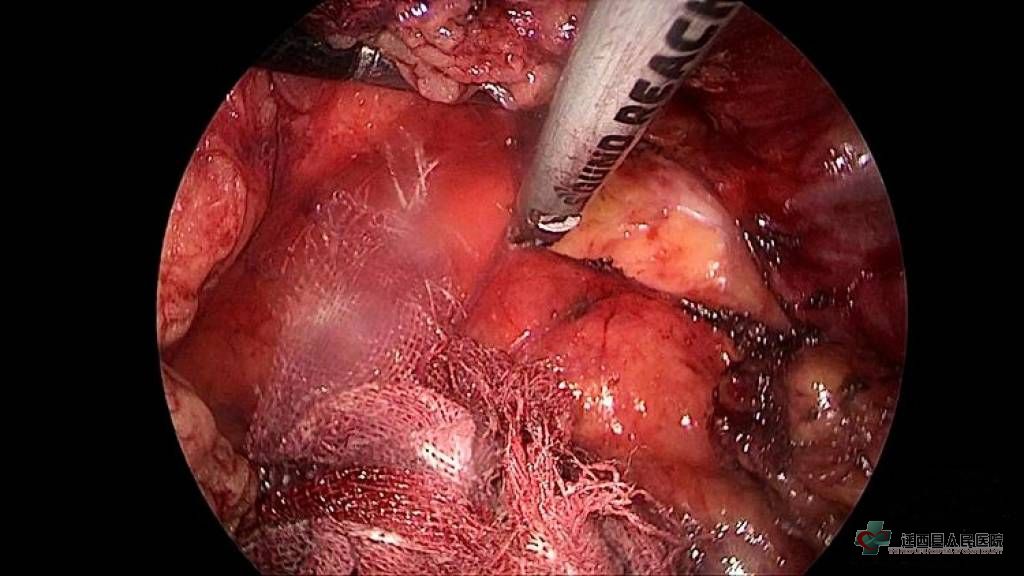

在彭永光副院长带领下,外二科团队圆满完成了我院首例腹腔镜下输尿管切开取石术,患者病情治愈满意而归。 术中情况:

腹腔镜下游离输尿管

切开输尿管取出结石

植入支架管预防输尿管狭窄及输尿管漏

腔镜下完美缝合输尿管